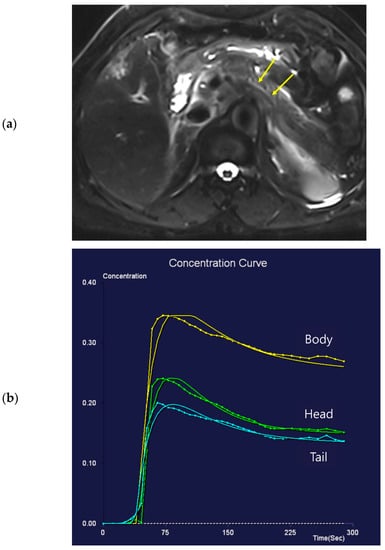

Figure 2. Seventy-one-year-old female patient undergoing an MRI to evaluate the gall bladder. There is no pancreatic dilatation (arrows) on the T2-weighted imaging (a) and no pancreatic focal lesion. Dynamic contrast-enhanced curves show rapid peak-enhancement and a gradual decrease in enhancement in the head, body, and tail (b).